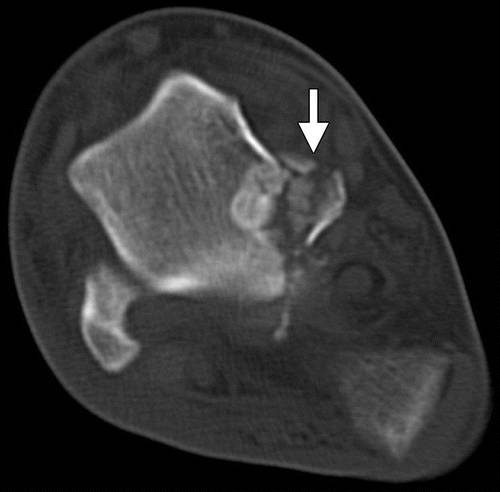

根据Hawkins标准,横突骨折最常分为三种类型:简单(I型),粉碎型(II型)和切片(III型)(图15)(33)。 类型I,最常见的,由具有从踝关节表面延伸到距下关节的单个断裂线的大片段组成(图16)。 类型II是涉及整个侧向过程和两个关节表面的粉碎性骨折(图17)。 III型骨折发生在窦性the骨区域,并且通常仅在横向X线照片上可视化。

图17a Hawkins II型距骨横突骨折。 (a)踝的AP射线照片显示横突的断裂(箭头)。 (b)冠状重建的踝关节的CT图像显示了涉及整个横突(箭头)的粉碎性骨折。

保守地治疗非置换侧向过程骨折。 如果存在大于2mm的位移(37),则指示开放还原内固定(ORIF)。 大于1cm的碎片通常可以用内固定治疗。 小的粉碎片段可能需要被切除。 外科治疗降低继发性距下关节骨关节炎的风险并改善结果(3,38)。处理方法取决于侧向过程断裂的尺寸和粉碎和位移的程度。